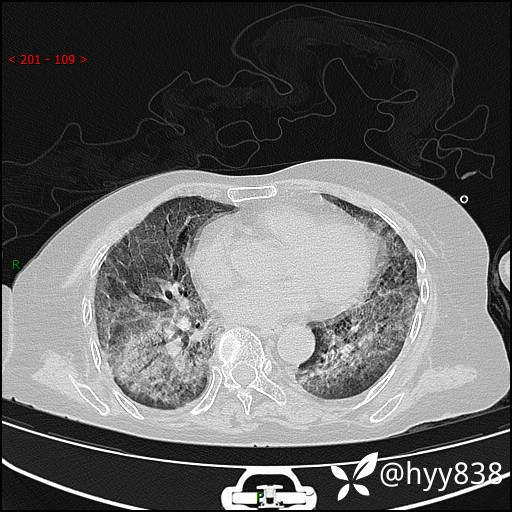

弥漫性肺部病变,辗转当地多家医院未能确诊,拟诊“重症肺炎”入我院--结果公布

患者年龄:69岁

简要病史: 患者20余天前无明显诱因出现发热,最高体温37.5℃,伴头晕,乏力,纳差等不适,无鼻塞,流涕,无咳嗽咳痰,无呼吸困难,无恶心呕吐、关节疼痛等不适,于当地市多家医院就诊,未明确病因,2023.6.23于当地第二人民医院就诊,完善胸部CT示病毒性肺炎,予以抗感染、清热解毒后症状较前稍好转,2天前患者无明显诱因出现活动后喘息加重,伴肌肉酸痛,口干,无明显咳嗽咳痰,今日体温38.1℃,为求进一步诊治来我院就诊,门诊以“ 重症肺炎 I型呼吸衰竭”收入院。 患者起病以来,精神、睡眠、饮食欠佳,大小便正常,体力下降,体重无明显改变。

辅助检查:CT

临床诊断:重症肺炎

胸部CT薄层扫描